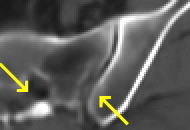

To test the impact of the iterative refinement on YODA’s translation quality, we compared regression and diffusion sampling on the RS data and present additional generation examples in Fig. 6. We observe that diffusion sampling visually resembles the appearance of the acquired images. Regression sampling preserves key anatomical features – the GM/WM boundary, WMHs (Fig. 4), the outline of the pallidum (Fig. 6) – but omits many high-frequency features. To investigate whether iterative refinement during diffusion sampling adds relevant and systematic medical information or only imitates acquisition noise, we performed ExpA sampling, i.e. averaging the output of several ( or ) diffusion trajectories. We observed a gradual loss of high-frequency details when increasing the (see also the supplementary video), indicating that the effect of the iterative refinement is non-systematic. For , the images are visually almost indistinguishable from the initial regression solution (see the supplementary video, and Fig.4 and 6). We directly compared the synthesis results of ExpA () and regression sampling quantitatively and found the differences to be minimal (SSIM: 99.73%, PSNR: 45.30 dB), i.e. diffusion sampling approaches the initial regression solution for a high . The quantitative analysis of the image quality (Tab. 1) showed that diffusion sampling impairs the assessed SSIM and PSNR in comparison to regression sampling for both the in- and external test sets, which we attribute to noise generation (Sec. 3.1). In turn, ExpA averages improved both metrics and, for , performed mostly on par with the regression solution in both test sets in terms of SSIM, while the PSNR in the RS was slightly increased (Tab. 1). However, we observed that ExpA sampling YODA improves the replication of systematic 3D low-frequency image intensity drifts (bias fields) due to the 3D synchronization in 2.5D diffusion sampling. Yet, this apparent advantage did not generalize to the external MBB dataset, as bias fields are MR protocol-specific.

To assess the suitability of YODA-generated images for WMH detection independent of segmentation tools, we also calculated the CNR (15) of WMHs. This confirmed that the contrast of WMHs is preserved in the regression images, whereas we noted slightly reduced WMH contrast for diffusion and ExpA-sampled images (Tab. 1).

However, we observed some missing small WMHs (third row, Fig. 9) in the synthetic FLAIR images. Due to the weak input signal, translating small WMHs in inherently difficult and, thus, omitting these WMHs can be seen as conservative. In contrast, a more speculative translation bears the risk of false-positive, hallucinated WMHs (compare e.g., SynDiff, Fig. 4).